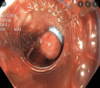

5 - gastroscopy